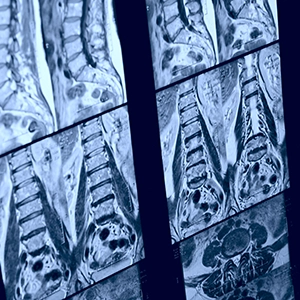

A wide-bore MRI is an advanced imaging machine designed with a larger opening, offering up to 20% more space than traditional MRI scanners. It delivers the same high-quality diagnostic images using powerful 3T and 1.5T technology, without using any radiation. With added comfort for those who may feel anxious, claustrophobic, or need extra room to remain comfortable, a wide-bore MRI makes your scan faster, easier, and more comfortable without compromising accuracy.

The 70 cm open-bore design offers extra space to help you feel more at ease. It comfortably accommodates patients up to 550 lbs. The shorter magnet length allows head-out exams to be possible for various parts of the body, including the lower extremities.

What to expect during your Wide-Bore MRI

When you arrive, one of our patient service representatives will check you in. Once called back, you may be asked to change into a gown to ensure the best image quality and safety, especially if your clothing contains any metal. Once you’re ready, you’ll be comfortably positioned on a padded table that slides gently into the scanner. The wide-bore design will provide you with extra space around your head and body. Depending on the area of the body being scanned and if contrast was used, the scan usually takes between 15 – 60 minutes.

Throughout the study, you will be in constant communication with the technologist, who will guide you and ensure you are at ease. Once complete, your images will be reviewed by a board-certified radiologist and sent directly to your referring provider for follow-up.